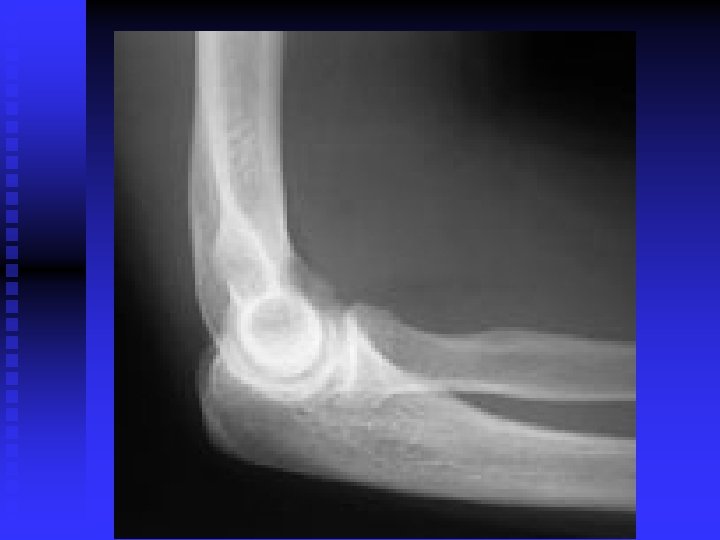

Elbow

Ulnar Neuritis n Pathology u Superficial position at the elbow u Excessive pressure in this area u Second most common entrapment neuropathy in the upper extremity

Ulnar Neuritis n Mechanism of injury u Compression of the ulnar nerve: cubital tunnel (epicondyle, olecranon, MCL, arch of arcuate ligament and of 2 heads of FCU u Elbow flexion tightens arch u Repeated rapid activities such as throwing and prolonged flexion may traction or compress nerve u Nerve can sublux out of tunnel

Ulnar Neuritis n Clinical signs and symptoms u Sensory changes in classic ulnar distribution: little finger and ulnar side of ring finger u Positive elbow flexion test u Positive Tinel’s test u Weakness of grip u Deterioration of 2 point discrimination u Adductor Pollicus neuro-weakness u Neuro-weakness interossei (Wartenburg)

Ulnar Neuritis n Common treatments u Non-operative: rest is imperative; NSAIDS; determination of cause and elimination of it u Surgical intervention: decompression or transposition